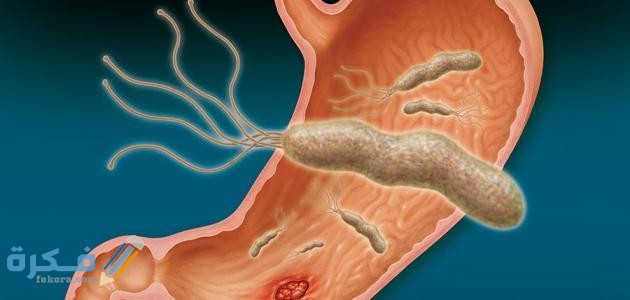

أكمل القراءة »الأدوية التي تؤثر على تحليل جرثومة المعدة ، حيث أن هناك بعض الأدوية التي تؤثر على تحليل جرثومة المعدة ويتطلب…